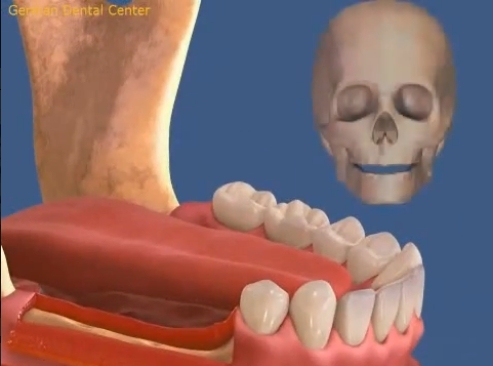

- Имплантация